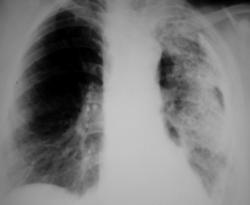

Иллюстрации 1, 2. Тотальное снижение прозрачности легочной ткани слева значительной интенсивности, неоднородной структуры. Средостение несколько смещено влево. Справа определяется компенсаторная эмфизема, слева умеренно выраженный плеврогенный цирроз.

Иллюстрации 3, 4. Фрагменты рентгенограмм с увеличением. Структура затемнения неоднородная, ноздреватая. На боне интенсивного затемнения визуализируются округлые участки просветления. Местами определяются более интенсивные участки затемнения известковой плотности в виде «очаговости».